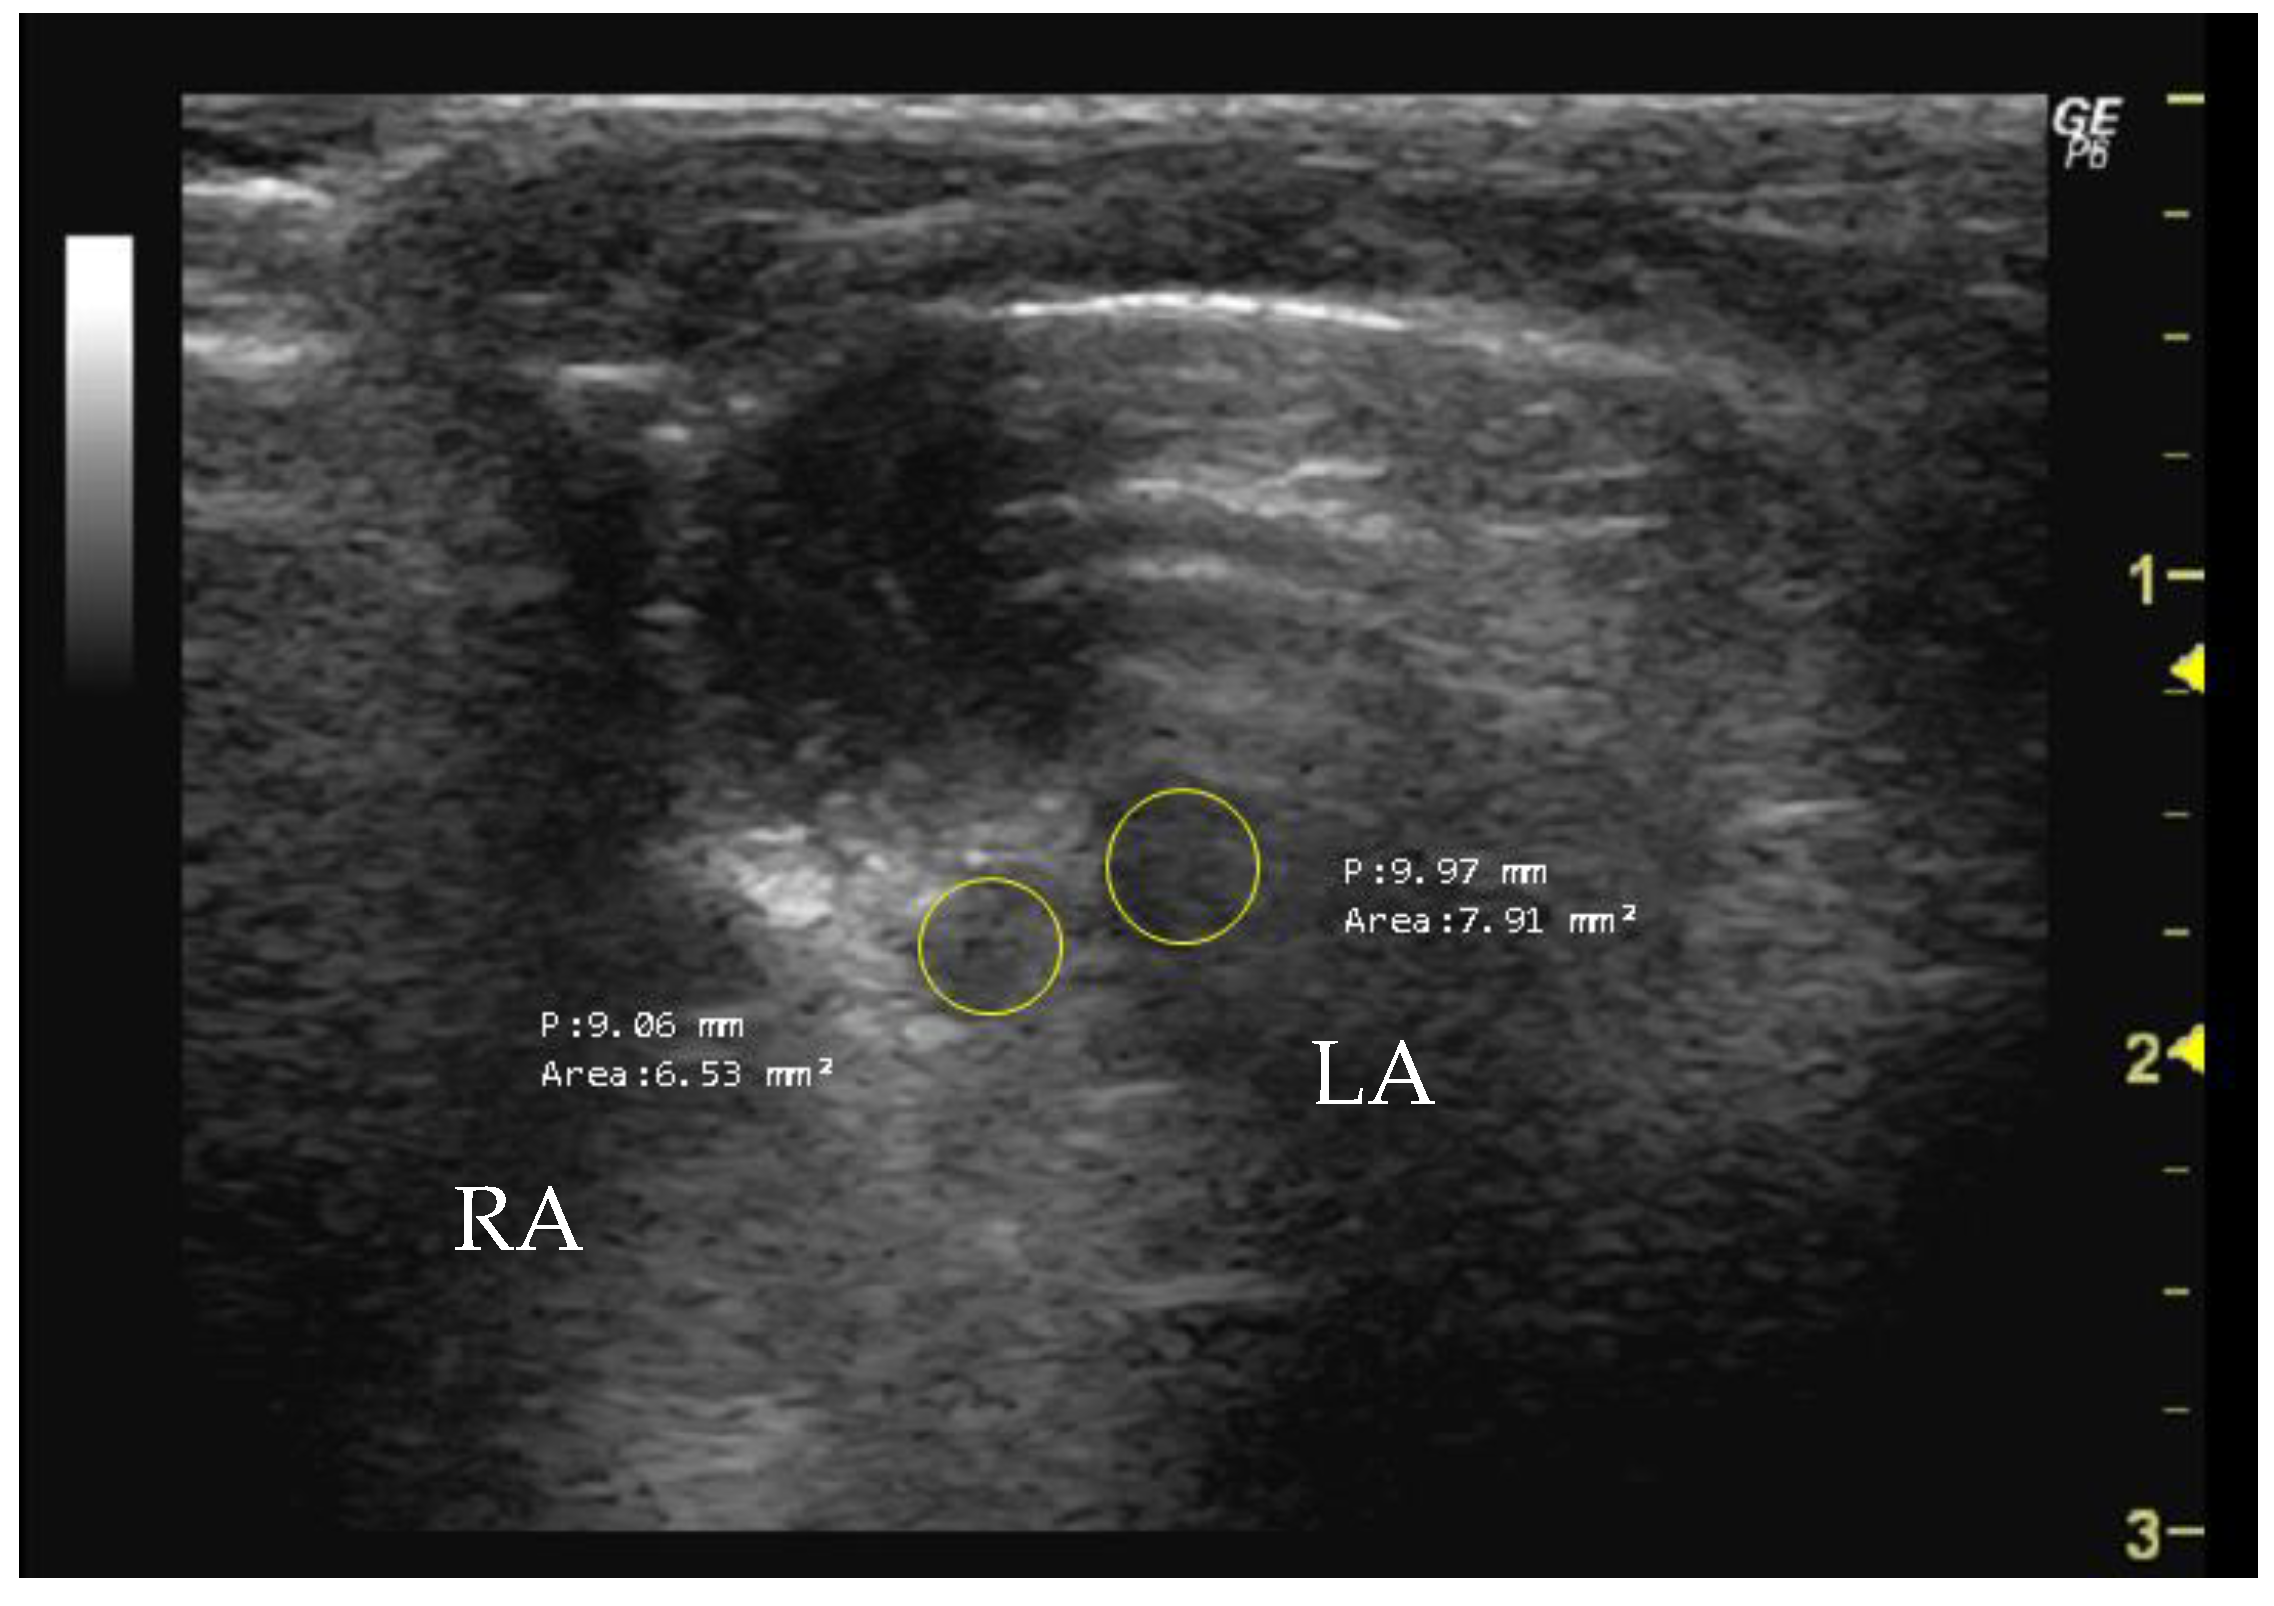

- How to measure RA and LA